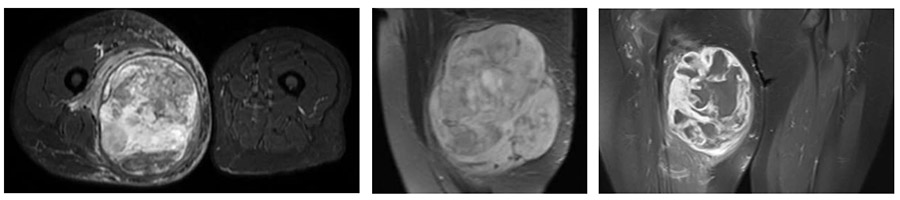

Ameliyat Öncesi: MR’da uyluk iç kısımda sınırları düzensiz, heterojen yumuşak doku kitlesi ve çevreleyen ödem görülmekte